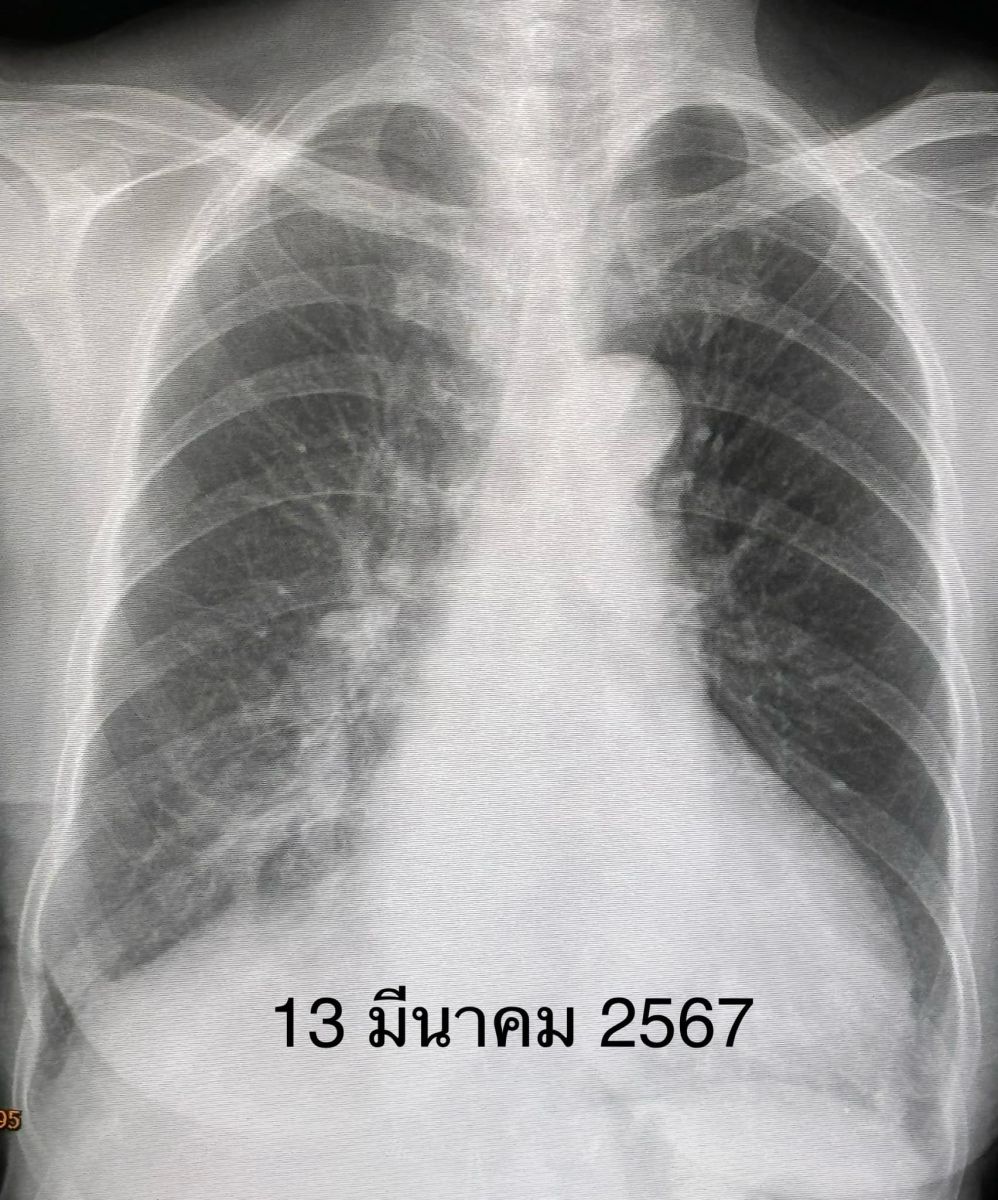

ตรวจร่างกาย อุณหภูมิ 38 องศาเซลเซียส ระดับออกซิเจนปกติ 96% ฟังปอดปกติ ส่งตรวจรหัสพันธุกรรม 22 สายพันธุ์ พบเชื้อไรโนไวรัส (Rhinovirus) เพียงตัวเดียวเอกซเรย์ปอดพบฝ้าขาวที่ปอดด้านขวาล่าง (รูปวันที่ 4 มี.ค.2567) เจาะเลือด เม็ดเลือดขาวปกติ ส่งเพาะเชื้อในเลือดไม่ขึ้นเชื้อแบคทีเรีย

วินิจฉัย : ปอดอักเสบจากเชื้อไรโนไวรัส (Rhinovirus) ให้ยาสเตียรอยด์ขนาดต่ำๆ 5 วัน ผู้ป่วยดีขึ้น ไม่มีน้ำมูก ไม่เจ็บคอ ไม่มีไข้ ไอลดลง เอกซเรย์ปอดฝ้าขาวลดลง (รูปวันที่ 8 มี.ค.2567) นอนในโรงพยาบาลทั้งหมด 5 วัน ติดตามหลังจากออกจากรพ. 5 วัน ไอน้อยลงมาก เอกซเรย์ปอดฝ้าขาวด้านขวาล่างลดลงอีก (รูปวันที่ 13 มี.ค.2567)